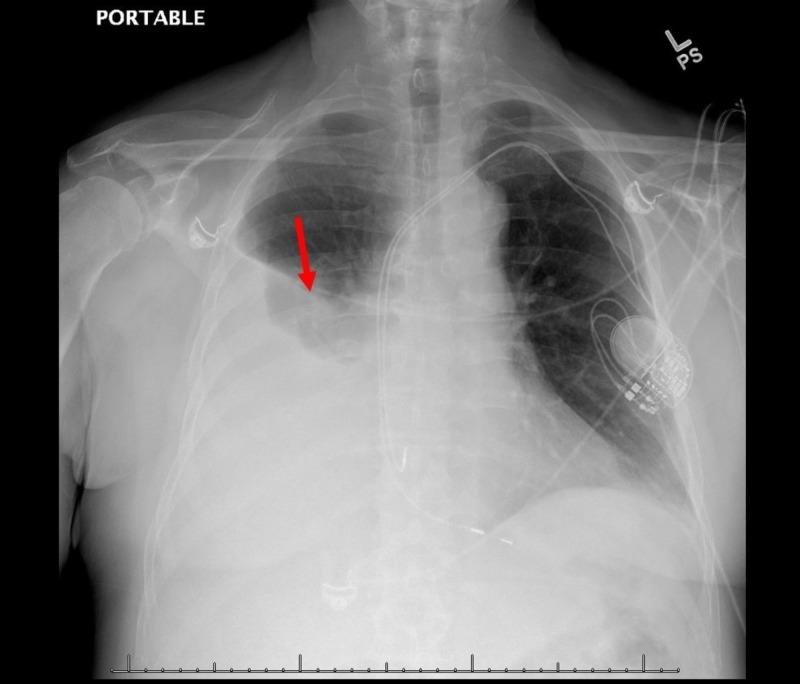

Post-cardiac injury syndrome (PCIS) as a delayed complication of permanent pacemaker implantation has rarely been reported in the literature. A 67-year-old man who recently underwent a dual chamber permanent pacemaker implantation came to the hospital for increasing dyspnea and chest discomfort. A diagnosis of pericarditis was made, and the patient was discharged on ibuprofen therapy. He presented to our facility a month later with worsening dyspnea and chest discomfort despite recommended therapy. A computerized tomography (CT) scan of the chest revealed a large right-sided pleural effusion, requiring chest tube placement and drainage. A pleural fluid analysis revealed exudative effusion with elevated pH. The pleural fluid analysis was negative for infectious etiology. A perforation of the atrial wall was considered given the proximity of the atrial pacer lead and overlying pericardial effusion. However, no conclusive evidence of cardiac chamber perforation was found on echocardiogram or CT scan. A pacemaker interrogation was normal. A repeat CT scan showed the resolution of pleural effusion, and the chest tube was discontinued. A possible explanation for the absence of predominant pericardial findings may be the previous use of non-steroidal anti-inflammatory therapy.

心脏损伤后综合征(PCIS)作为永久性起搏器植入的延迟并发症,在文献中鲜有报道。一名67岁男性近期接受了双腔永久性起搏器植入术,因呼吸困难加重和胸部不适前来医院就诊。诊断为心包炎,患者出院时接受布洛芬治疗。尽管接受了推荐治疗,但一个月后他因呼吸困难和胸部不适加重再次来到我们的机构。胸部计算机断层扫描(CT)显示右侧大量胸腔积液,需要放置胸管引流。胸腔积液分析显示为渗出性积液,pH值升高。胸腔积液分析未发现感染性病因。考虑到心房起搏器导线靠近且存在心包积液,怀疑心房壁穿孔。然而,超声心动图或CT扫描均未发现心腔穿孔的确切证据。起搏器程控检查正常。重复CT扫描显示胸腔积液消退,胸管拔除。心包主要表现不明显的一个可能解释是先前使用了非甾体抗炎治疗。